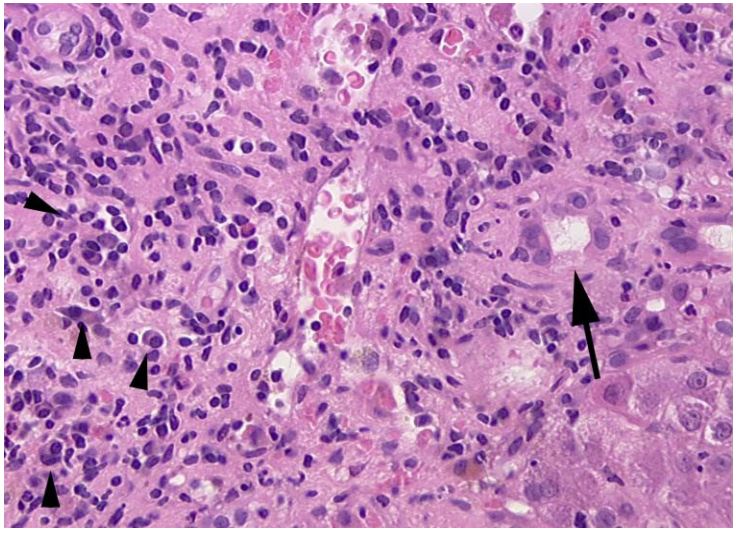

Figure 3 & 4: 4 months later, centrilobular cholestasis was major (arrow head) and the loss of bile duct was definite, confirmed by CK7- immunostaining which showed no duct inside the portal tract and a clear periportal biliary metaplasia (severe ductopenia).